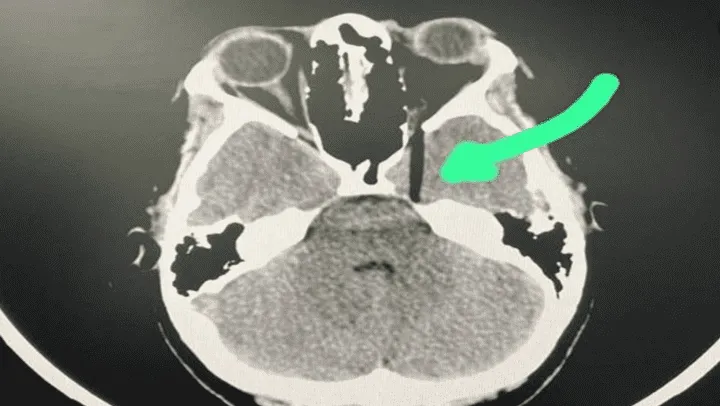

Las risas inundaron la habitación, hasta que la joven levantó el rostro y los presentes se horrorizaron: ¡El palillo de bambú se le había incrustado en uno de los ojos! Enseguida, la chica fue trasladada al hospital, donde fue internada y sedada.

En diálogo con la prensa, la hermana de la víctima, quien solicitó que no se publicaran nombres ni datos personales de ninguno de los involucrados, dio detalles de la desesperante experiencia y descartó que su familiar hubiera sufrido la pérdida del ojo y daño cerebral a pesar de la gravedad del accidente.

Las autoridades del hospital en el que se encuentra internada la joven informaron que la paciente fue operada y se encuentra estable en la Unidad de Cuidados Intensivos.